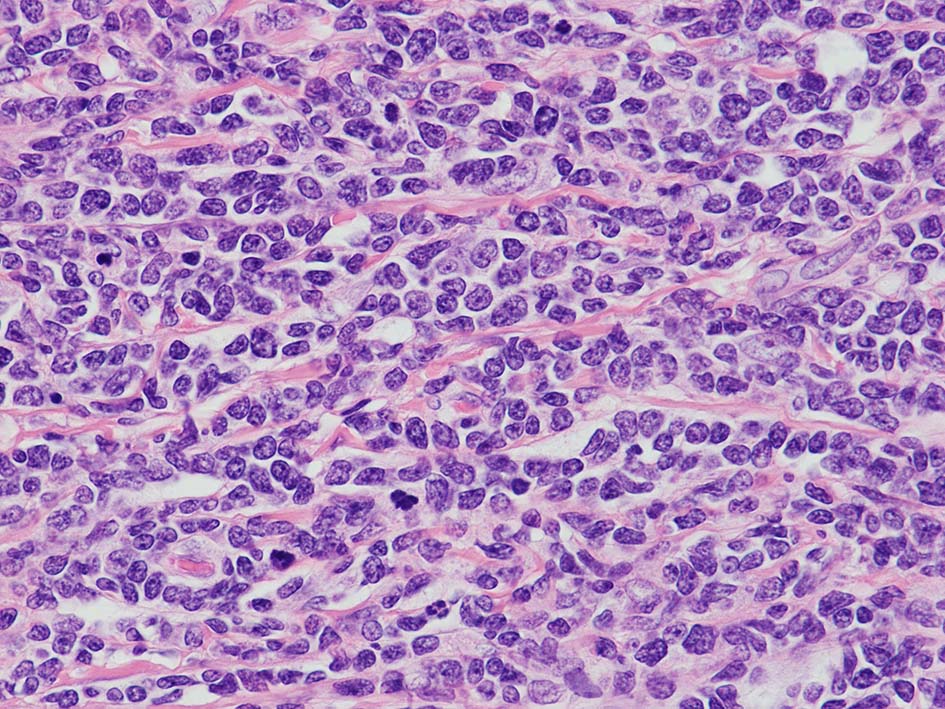

loupe像Aの領域: 精細管をスペアするように, 小型リンパ球優位, 一部中型のlymphoid cellsがシート状密に浸潤増殖する. tubulesのほとんどにはlymphoid cellsが浸潤していないが, LELに似たようなlympho-tubular lesionが少数認められた. x400高倍率では, 増殖細胞は, 粗く, 凝集したクロマチンをもつ類円形, non-cleavedな核をもつ細胞質の乏しいlymphoid cellsである. 核小体か凝集したクロマチンかわかりにくい.

白膜には密に腫瘍性リンパ球が浸潤増殖し, 肥厚, 一部は上図loupe像のように, 腫瘤を形成している. 浸潤リンパ球は精巣実質内よりも, やや大きく, 多稜形, くびれのある核をもち, クロマチンは淡明で核小体が明瞭になってきている.

細胞形態に惑わされてしまった. T-LBLの細胞はもっと幼若な形態を示すと思い込んでいた(Blue bookに成熟細胞の形態があると書いてあった!!)ため, 精巣実質浸潤T-cellをmature T-cellと考えてしまった. 臨床科からはホルマリン固定標本が提出され, FCM, 核型検査が行えていなかった.

CD4, CD8 double positiveはPTCL,NOSとして一般的ではないが, 腫瘍T-cellのabberant expressionかと考えた. CD10はPD-1, BCL6がうっすらと染まったため, follicular helper T-cellのphenotype?とした. CD8陽性細胞はcytotoxic molecules陰性で幼若な状況と考えず, 異常なCD8と推察した.